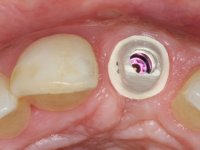

3) Colocação de um implante no espaço criado na zona do 21 associada a uma regeneração óssea guiada da zona,

4) Reabilitar prostodonticamente o implante com um coto de oxido de zirconio e uma coroa de cerâmica vítrea prensada de dissilicato de lítio no sentido de obter o resultado estético pretendido.

Os cotos de óxido de zircónio são dos assuntos mais debatidos em implantologia. A sua resistência à fractura, as conexões externas e internas, a interacção entre o parafuso de retenção e o coto – todos estes assuntos são abordados repetidamente. No entanto, todos parecem concordar que os cotos de óxido de zircónio apresentam resultados altamente previsíveis, especialmente na restauração de dentes anteriores. Outro argumento em favor dos cotos de óxido de zircónio é a alta biocompatibilidade do material.

A comparação entre o óxido de zircónio e o dissilicato de lítio mostra que o último pode sofrer ataque ácido e ser silanizado e assim ser preparado para uma cimentação adesiva. Uma dica: no sentido de criar no coto de óxido de zircónio uma superfície susceptível de ser gravada pelo ácido, a superfície a ser colada pode ser recoberta com uma fina camada de cerâmica de adesão antes de modelar a coroa. Para este propósito, a ceram Zirliner é aplicada primeiro, depois aplica-se uma camada de ceram de dentina profunda na tonalidade desejada. Como resultado, a cor da dentina ilumina a restauração a partir do seu interior e cria a possibilidade de ser aplicado um protocolo de cimentação adesiva.